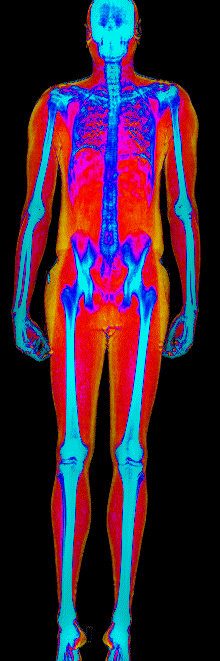

This page features real, anonymized DEXA scan images from BodyStats clients, organized by gender and body fat percentage in 5% increments. DEXA (Dual-Energy X-ray Absorptiometry) is the clinical gold standard for measuring body composition — far more accurate than scales, calipers, or visual estimates.

Each colorized scan shows the distribution of fat tissue (shown in warmer colors) and lean tissue (cooler colors) throughout the body. Compare your own DEXA scan to others in your range, or see what different body fat levels actually look like on a scan.

Male DEXA Scans by Body Fat %

25 to 30% body fat